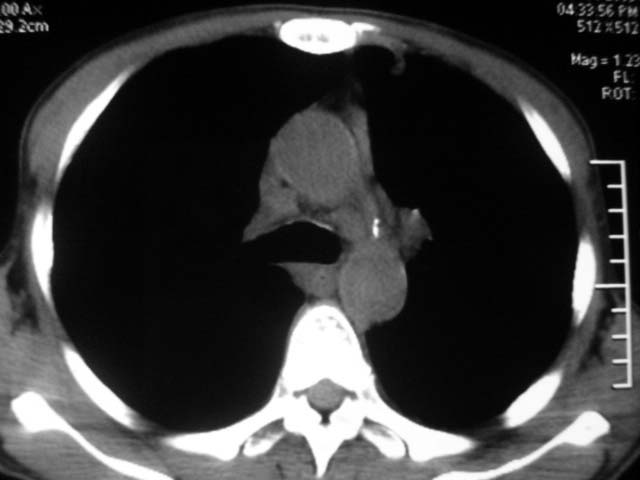

男,52岁,发热2月,糖尿病史。

抗结核治疗irpz方案,血糖未治疗,空腹15.9左右。症状无好转,左胸痛。

复查ct

2、双肺见多发片状及结节状高密度影,大多数病灶中心均见“空泡征”。

3、纵隔内淋巴结肿大。

结果:两肺继发性肺结核并曲霉菌感染。